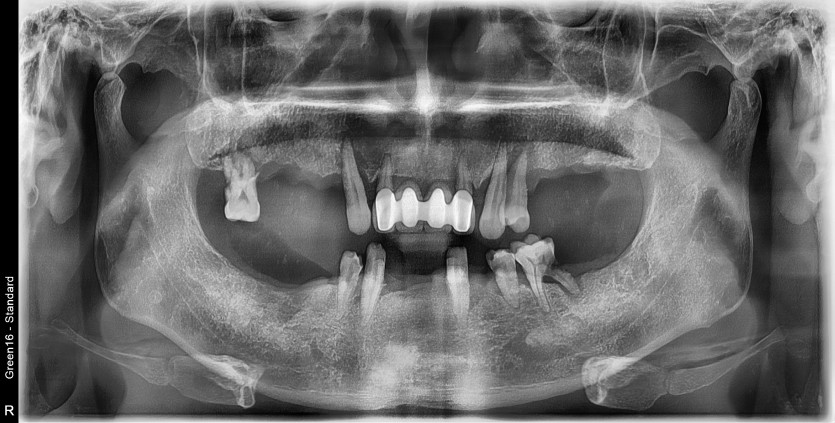

만 56세 전체 임플란트 증례

전체 임플란트 증례입니다.

18개의 임플란트로 완성하였습니다.